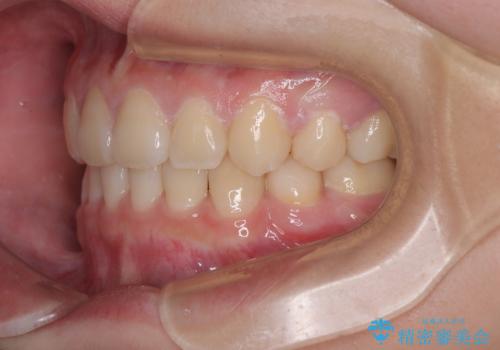

結果的に1年半で、再度転勤になる前に治療を終えることができました。

- 転勤により東京へ移られることになり転院先を探されていた患者様です。ワイヤー矯正の途中での急な転勤なうえ、今後2~3年以内に再度転勤になる可能性もあるというご事情でした。

そのため、限られた期間内に効率よく治療を完了するために、「抜歯スペースの確実な閉鎖」「深い噛み合わせ(過蓋咬合)の改善」の2点を主軸とした治療計画を立てました。